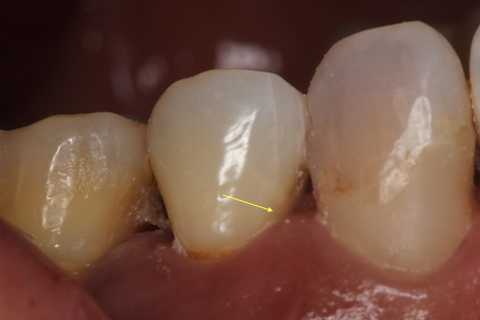

以下は術前の画像だが、5番にも6番にもクラックはあるので、これだけではどちらが沁みているのか特定できない。

5番には術中から気になっていた大きなクラックが認められたので、この部分は裏面の軟化象牙質はエナメル質を壊さないように丁寧に除去してCRで裏打ちし補強を入れた。